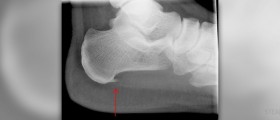

Plantar fasciitis surgery recovery

Plantar Fasciitis - OverviewPlantar fasciitis is the medical condition of, inflammation of the plantar fascia. The condition is generally treated conservatively and to provide the desired results, if all else...